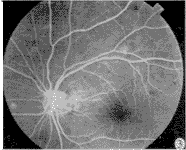

上述观察组治疗前后荧光素眼底血管造影变化,表明了中西医结合治疗,有助于消除或 减轻 毛细血管、微动脉瘤、色素上皮的渗漏,但水肿范围越大,病情越重,效果越差。典型病例 介绍见图1~图3。

图1 典型病例治疗前眼底普通像 图2 治疗前荧光素眼底血管造影像

图3治疗后黄斑水肿消失